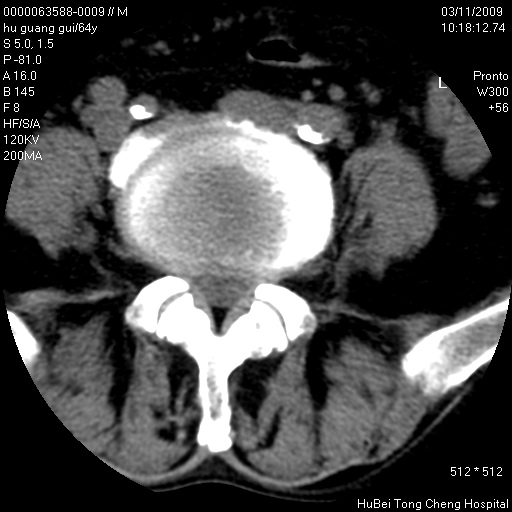

患者 男,64岁。腰痛十余天。(临床未提供其他病史)

临床诊断:腰痛原因待查(腰椎间盘突出症?)。

腰椎间盘ct轴位平扫(层厚5mm,层距4mm),图像如下:

腰椎退行性变,腰4—5椎间盘膨出。

右侧骶骨侧块骨侵蚀,骶髂关节骨性关节面破坏,并见软组织肿块,考虑骨转移瘤可能,进一步检查。

1.腰椎退行性变,腰4—5椎间盘膨出。

2.右侧骶骨侧块骨侵蚀,骶髂关节骨性关节面破坏,并见软组织肿块,考虑:脊索瘤,骨转移瘤可能,进一步检查。

1)腰椎退行性变,l4—5椎间盘膨出。2)骶骨右侧块骨转移瘤可能,3)水平骶椎。建议作一步检查。